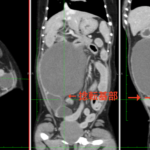

画像診断:特徴的な所見は述べらていませんが、CTで子宮の捻転基部が観察されました。

本症例は子宮水腫に続発した捻転と考えられました。ちいさな体で頑張ってくれました。